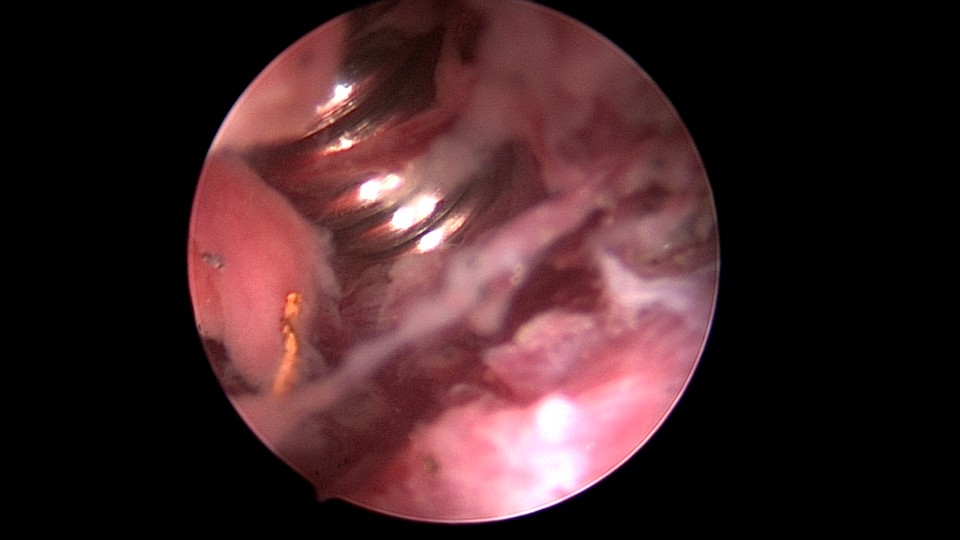

患者49岁,G1P1,顺产1次。安环13年,月经紊乱1月,外院取环失败。B超提示O型环嵌顿,宫腔镜见宫颈管及宫腔组织充血,宫腔广泛粘连,节育环嵌顿、扭曲,异物钳配合中弯钳拉出节育环,环变形、断裂,宫壁节育环嵌顿处见割裂痕迹,无出血,检查宫腔各部,无节育环残留。

图片发自160App